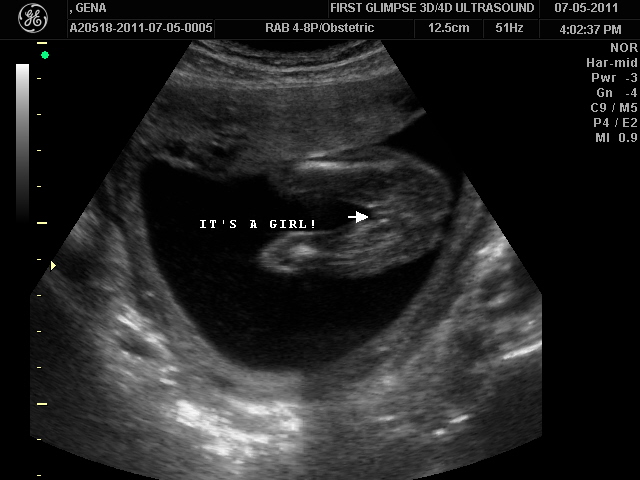

Today we had our Level II sonogram and I am happy to report that our little one appears to be perfectly healthy. So in other words she has everything she is supposed to and it is all in the right place :-). That is always reassuring to hear :-). She was weighing in at a whopping 1 pound and 1 ounce. Tiny as she might be she sure is active but I love it, every jab, poke, and kick brings a smile to my face.